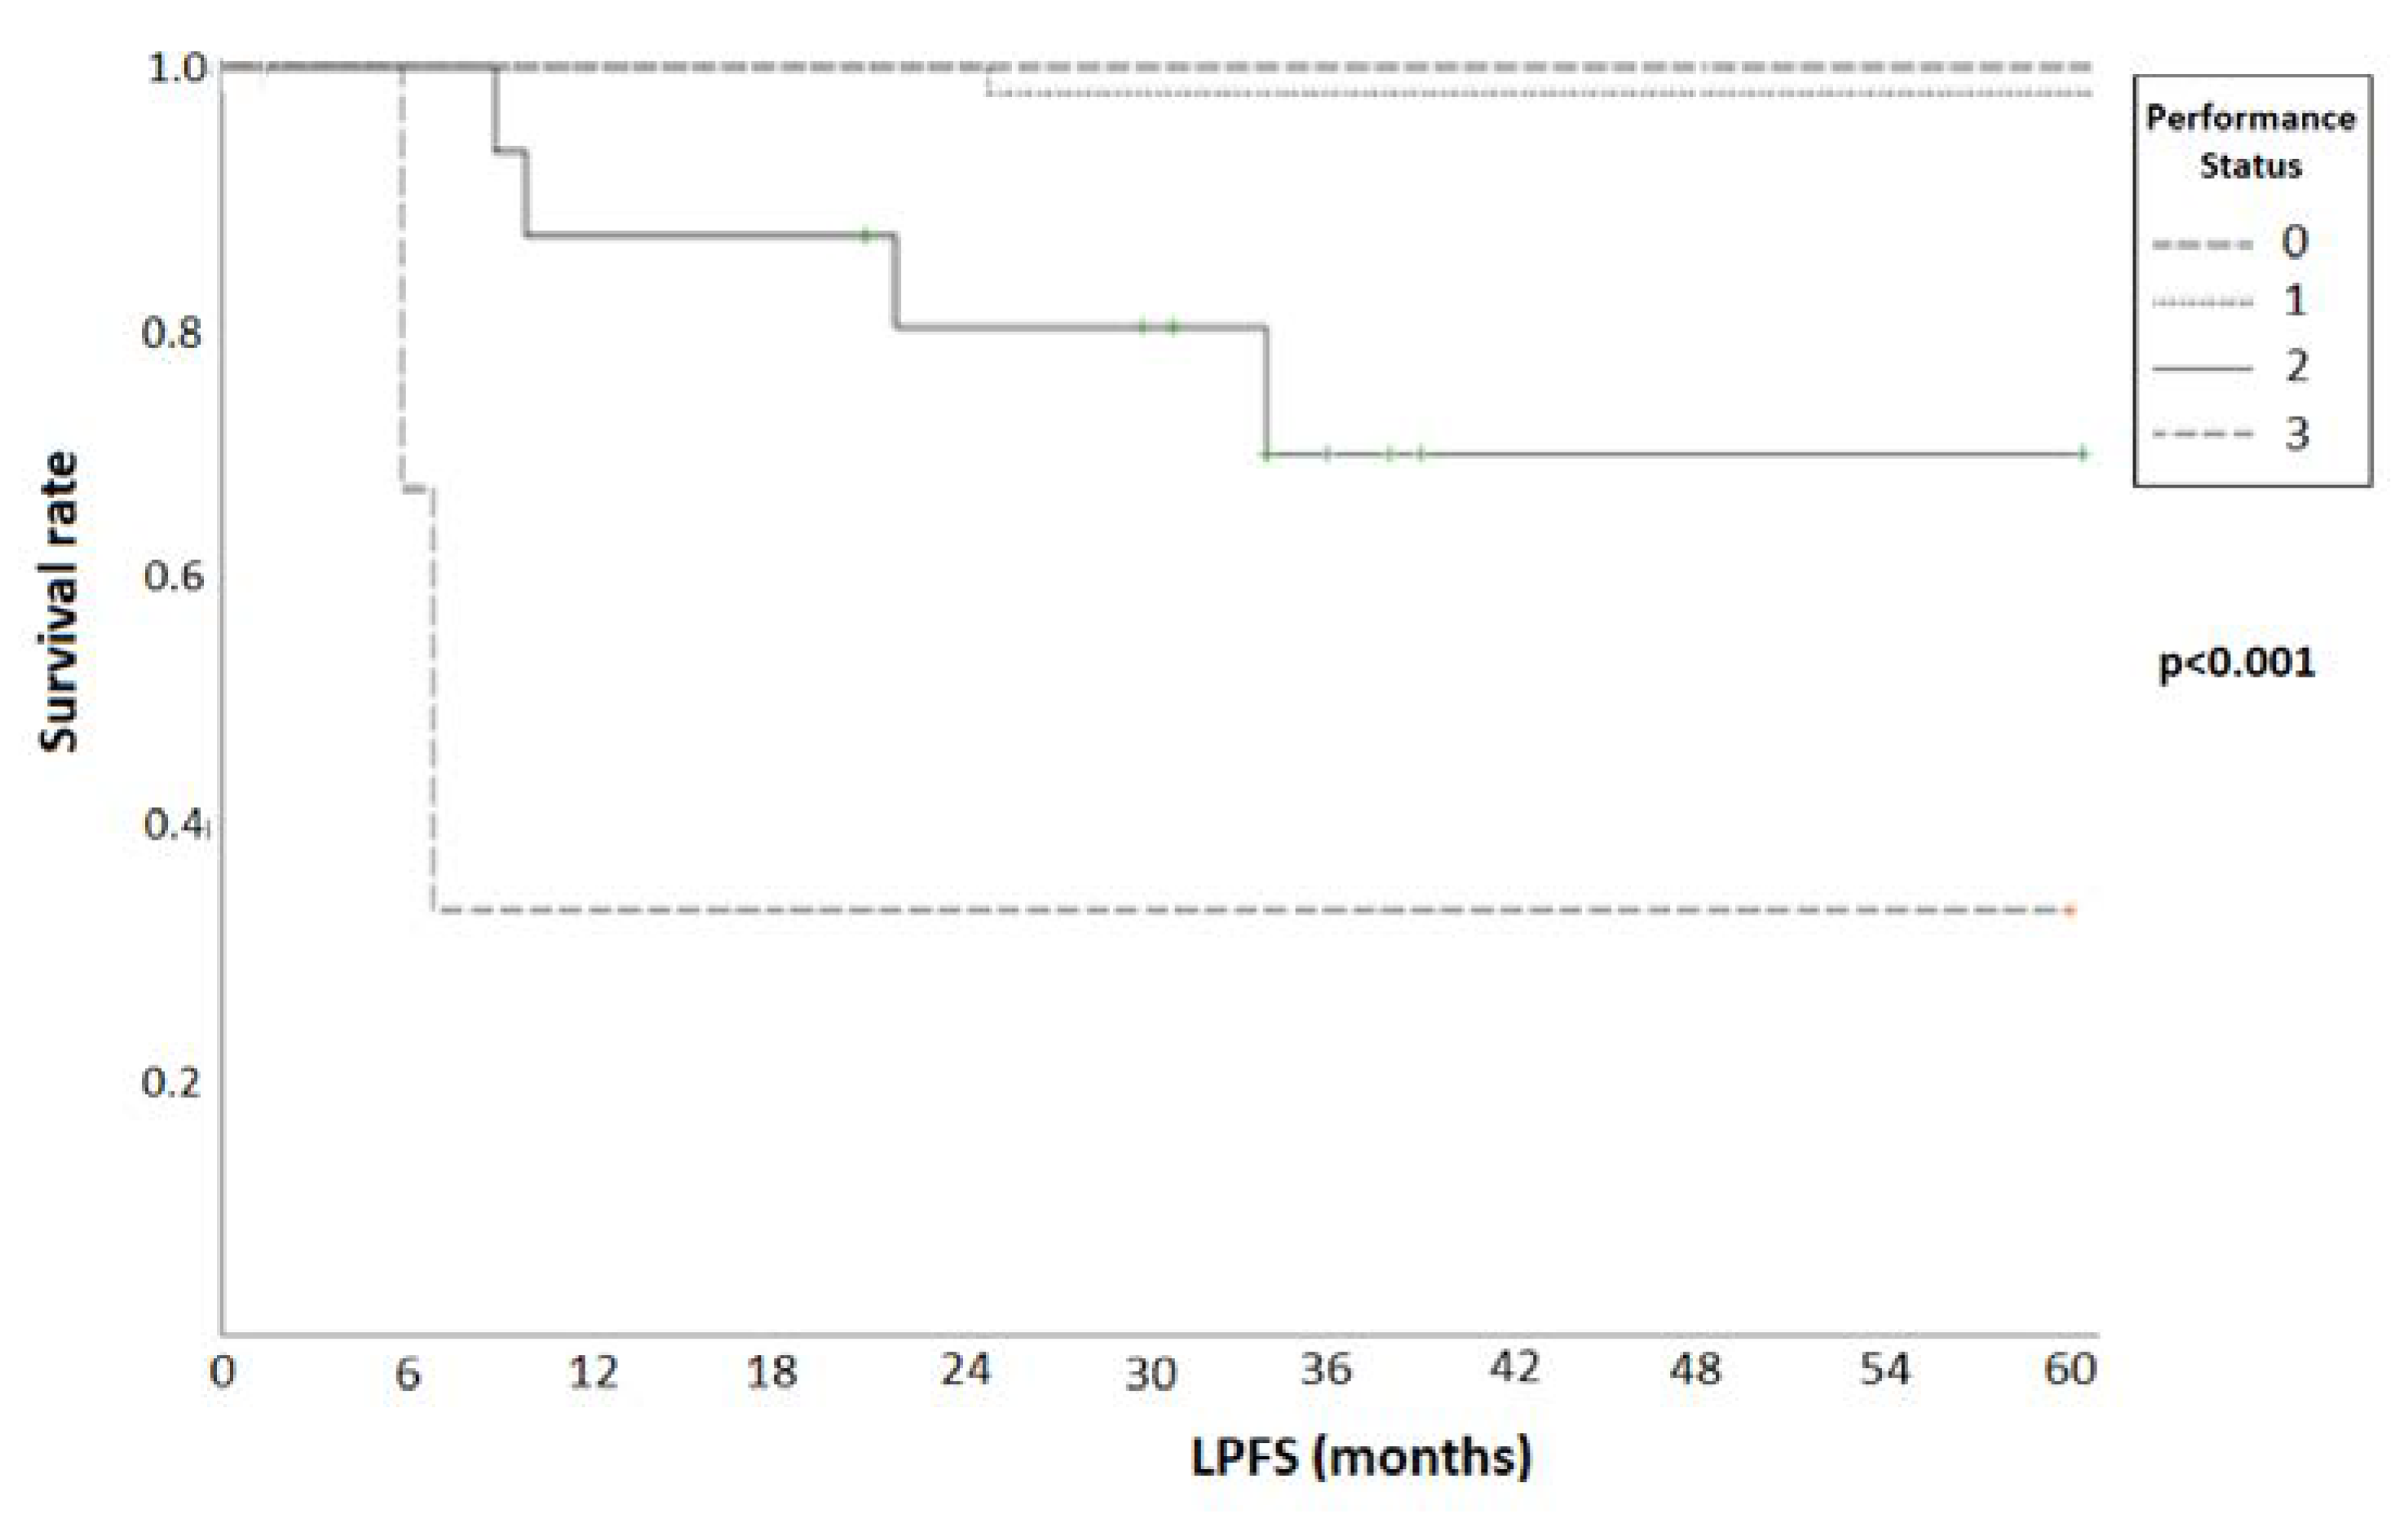

3.1. Treatment Response and Survival

| Univariate | Multivariate | |||||

|---|---|---|---|---|---|---|

| p | HR | 95% CI | p | HR | 95% CI | |

| Age | 0.41 | - | - | - | - | - |

| PS | 0.014 | 0.28 | 0.07–0.49 | 0.003 | 0.34 | 0.16–0.37 |

| TVI (cc) | 0.217 | - | - | - | - | - |

| Histological status | 0.89 | - | - | - | - | - |

| BEDα/β = 10 | 0.033 | 1.061 | 1.009–1.089 | - | - | - |